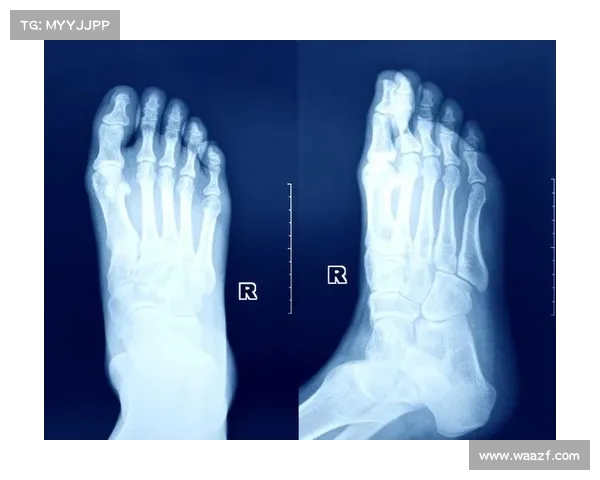

诊断方法与医疗检查

诊断脚部应力性骨折需结合临床检查和影像学检查。医生会先询问病史和症状,并进行体格检查,按压疼痛点以确认敏感区域。初期X光检查可能无法显示微小裂缝,因此常需使用更敏感的影像技术,如核磁共振(MRI)或骨扫描。MRI能清晰显示骨骼水肿和早期裂缝,而骨扫描则通过检测骨骼代谢活动来识别异常。对于高大体重球员,诊断时还需评估整体骨骼健康,包括骨密度检查,以排除骨质疏松等潜在问题。早期准确诊断至关重要,可避免伤病恶化并制定针对性治疗计划。